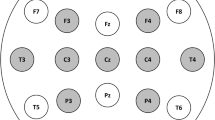

The 10-20 system is the only one officially recommended by the International Federation of Clinical Neurophysiology (IFCN) for the placement of all 21 electrodes [7]. The development of high-density EEG system and source localization methods (which refers to the use of 64–256 electrodes) has subsequently made necessary modifications of this system, and the 10-10 system has been accepted by the American Clinical Neurophysiology Society (ACNS) and IFCN for almost two decades (see Chap. 4) (Fig. 7.2) [8,9,10,11].

In the 10-10 system some electrodes from the 10-20 system were renamed: T3 and T4 were renamed to T7 and T8, and T5 and T6 were renamed to P7 and P8. In 2001, the 10-5 system was introduced [12], but the nomenclature was not yet formally accepted by the ACNS and IFCN. Very recently, the IFCN strongly recommends an array of 25 electrodes for standard EEGs including 6 electrodes of the inferior temporal chain (Fig. 7.3). The standard 10-20 system did not indeed include electrodes to record the activity of the inferior-basal and anterior part of temporal lobe. These electrodes are named, according to 10-10 system, F9-T9-P9 and F10-T10-P10 [11].

In conclusion, the 10-20 system is clinically adequate and efficient for routine standard EEG; the 10-10 system should be used in patients undergoing presurgical evaluation in Long-Term Epilepsy Monitoring Unit (LTEMU) or for additional digital analysis (i.e., electrical source imaging). Additional electrodes from the 10-10 system may also be used, sometimes, during standard EEG, especially to make a better localization of an epileptic focus.

For both clinical and educational purposes, it would be desirable to switch to T7/T8 and P7/P8 instead of T3/T4 and T5/T6, but the new terminology must be gradually accepted by the electroencephalographers and the EEG machine headboxes modified. At present, it would be an acceptable alternative to continue using the old terms or both [10]. In children, all 21/25 electrodes recommended for adults should be used [11, 13] even if, in the case of poor compliance or in critically ill children or for prolonged monitoring, the application of a smaller number of electrodes is also acceptable (Fig. 7.4).